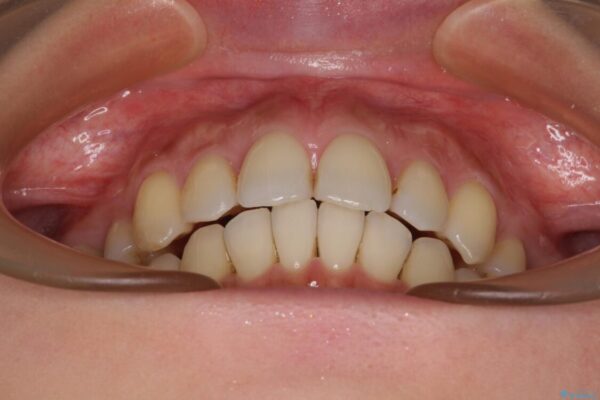

治療後

• 上顎前歯の突出を軽減 インビザラインによる抜歯矯正 治療後画像